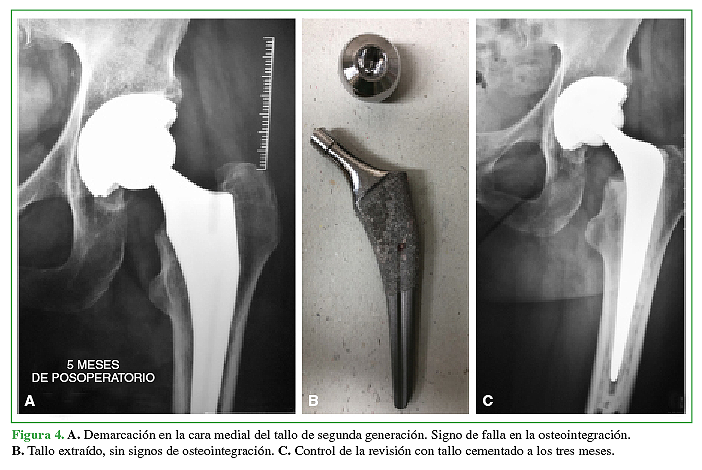

Un paciente (2%) de los 49 evaluados del grupo 2 requirió una revisión del tallo femoral por aflojamiento aséptico, a los cinco meses de la ATC primaria (Figura 4A y B). Se reemplazó por un tallo cementado (Figura 4C).

El paciente sometido la revisión protésica por aflojamiento aséptico del tallo femoral consultó por dolor, a los cinco meses. En ese momento, se constataron signos radiográficos de aflojamiento y se descartó una infección. Entonces, se procedió a la revisión en un tiempo, en la que se constató la ausencia de osteointegración del implante. Al no encontrar errores en la colocación, ni fallas en el implante, la única causa atribuible al aflojamiento fue que la paciente fumaba 40 cigarrillos por día, que como sabemos, afecta la microcirculación endóstica y puede dificultar la osteointegración. En los 48 pacientes restantes, se confirmó un correcto posicionamiento de los componentes y no se observaron signos de osteólisis o aflojamiento en el último control radiográfico.

A. Demarcación en la cara medial del tallo de segunda generación. Signo de falla en la osteointegración. B. Tallo extraído, sin signos de osteointegración. C. Control de la revisión con tallo cementado a los tres meses.